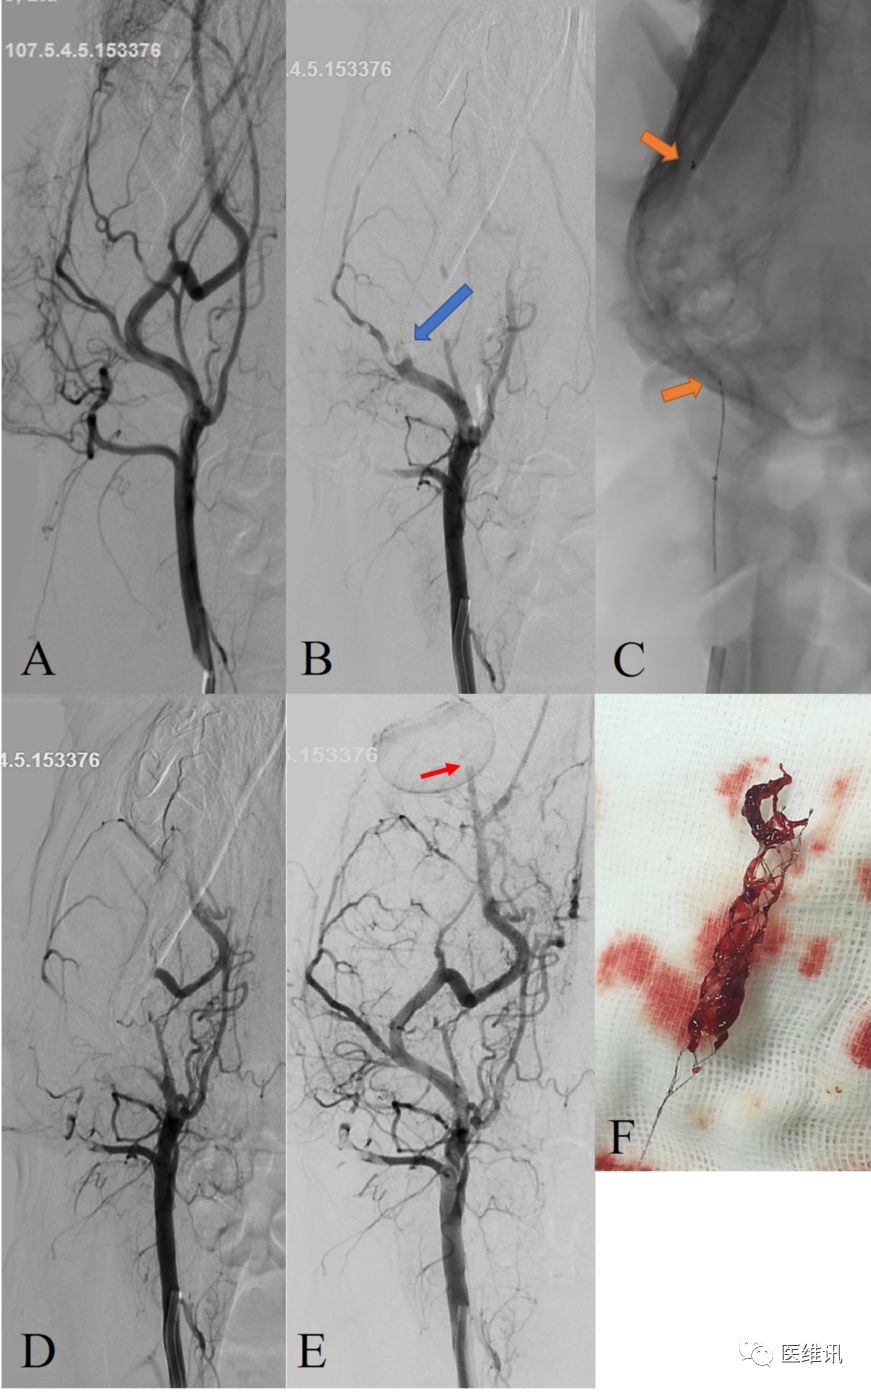

动物试验病例示例

动物模型取栓测试:犬类模型颈外动脉注入人工制备的血栓,造影确认堵塞目标血管,TICI血流0级。采用6F Envoy导引导管建立通路,分别使用Tonbridge通桥支架和Solitaire FR取栓支架统一型号4mm x 20mm进行取栓,并比较结果。